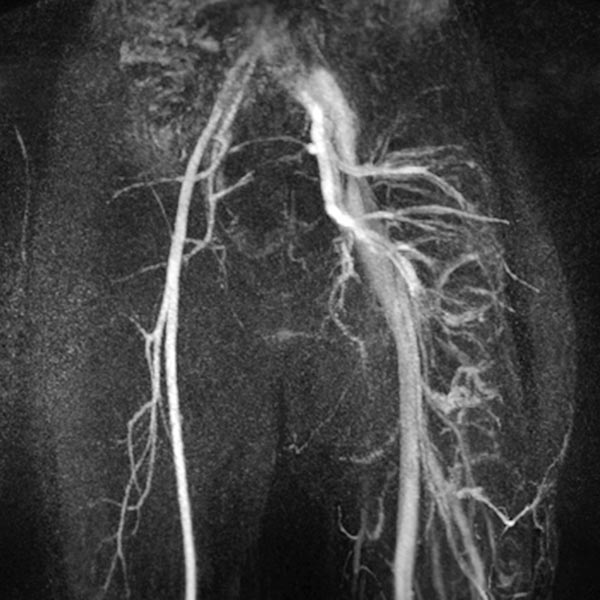

MIP-Rekonstruktion einer kontrastmittelunterstützen, dynamischen MR-Angiographie des Beckens und der Oberschenkel. Während auf der normalen rechten Seite hier noch eine arterielle Phase vorliegt, sind die Arterien und Venen der linken Seite massiv dilatiert und durch die multiplen arteriovenösen Fisteln des Parkes-Weber-Syndroms bereits die abführenden Venen kontrastiert.